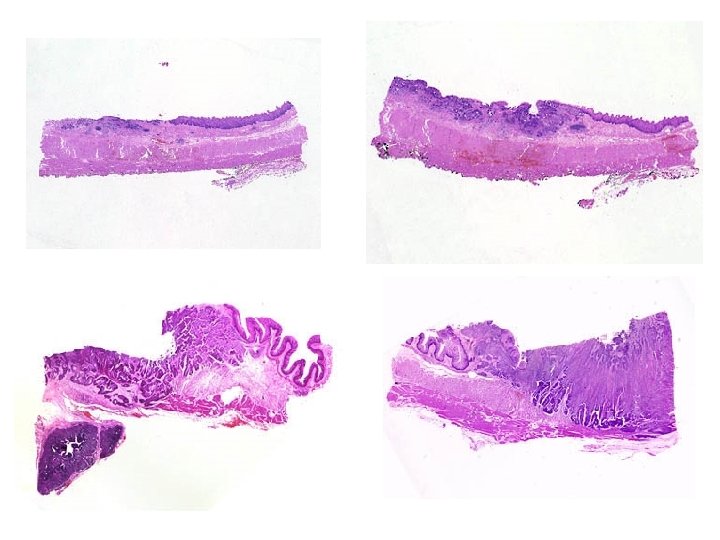

ESÓFAGO: E. BARRETT • ANATOMÍA PATOLÓGICA: – Presencia de células columnares mucosecretoras (metaplásicas) adyacentes al epitelio escamoso del esófago – Habitualmente lesiones parcheadas, por lo que requieren múltiples tomas de distintos zonas del esófago. • En la biopsia encontraremos varios fragmentos y en alguno de ellos, las células mucosecretoras. – Siempre se debe evaluar el grado de displasia epitelial por el riesgo de desarrollo de adenocarcinoma – Displasia: • Núcleos estratificados • Hipercromasia nuclear • Incremento de la relación núcleo/citoplasma • Atipia • Núcleos más redondeados que lo normal • Glándulas de morfología alterada

Azul alcián para demostrar mucina

E. Barrett con inflamación y cambios reactivos sin atipia

E. Barrett con displasia de bajo grado

E. Barrett con displasia de alto grado/adenocarcinoma